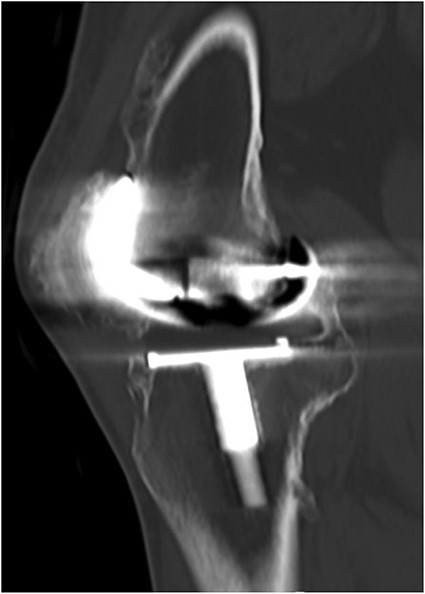

A 32-year-old female known case of rheumatoid arthritis affecting both knees presented to our clinic complaining of severe right knee stiffness post TKA 4-years-ago done in an outside facility (Figs. 1 and 2). She lives in a rural community and was on hydroxychloroquine, but her disease was active as she was not compliant to her medication. On physical examinations, the right knee was larger in size compared to the left knee without joint effusion. Range of motion was zero on flexion, −10° in extension. Standing knee X-ray showed HO around the prosthesis (Fig. 2). Computed tomography (CT) demonstrated extensive HO with implants fixed in place (Fig. 3). Revision surgery and replacement of the prostheses was considered to restore function.

Preoperative standing X-ray showing heterotopic ossification around the prosthesis with preserved knee joint. (A) Heterotopic bone extending proximally on the anterior surface of the femur. (B) Posterior heterotopic bone fusing the knee joint. Careful removal with osteotomes and bone curettes was necessary to remove the old implants.

CT demonstrated extensive heterotopic ossification involving the popliteal fossa, the anterior surface of the patella and at the distal third of anterior femur extending to the level of the knee-replacement prosthesis. There was no evidence of implant looseness or alignment deformity and there was no evidence of progressive ossification.